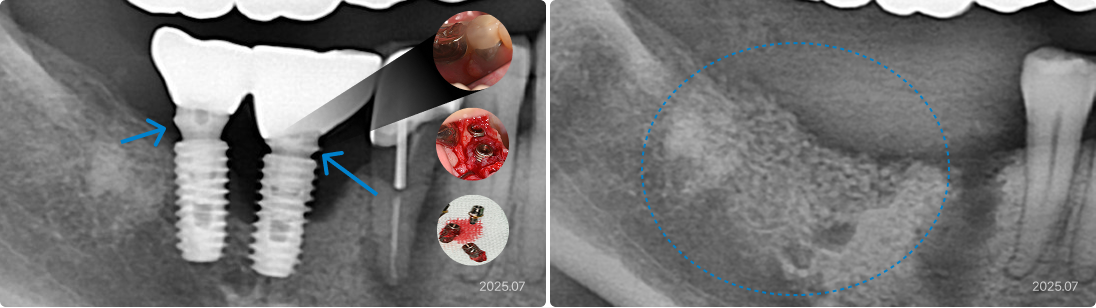

63세, 남 잘못된 치료 계획으로 인한 잇몸 문제

“임플란트 주변 잇몸이 계속 붓고 피가 나요.”

치료 전

• 적절하지 못한 크기와 잘못된 위치의 임플란트가 염증과 실패 유발

• 충분한 수의 임플란트임에도 불구하고 전부 다 연결되어 있어서

관리 및 치료가 불가능

• 하루라도 치아가 없이 지낼 수 없는 사회적 위치에서 위 턱의

모든 임플란트와 치아를 제거해야 하는 어려운 상황

치료 후

• 3D CT로 사전에 잇몸 뼈 상태를 정밀하게 분석, 재식립할 위치와

치료 계획 설정

• 수면 마취 하에 위 턱의 모든 임플란트와 보철물을 제거, 염증 깨끗하게

긁어냄

• 전악을 즉시 재식립, 디지털 임플란트 시스템으로 하루 만에 고정성

임시치아 장착